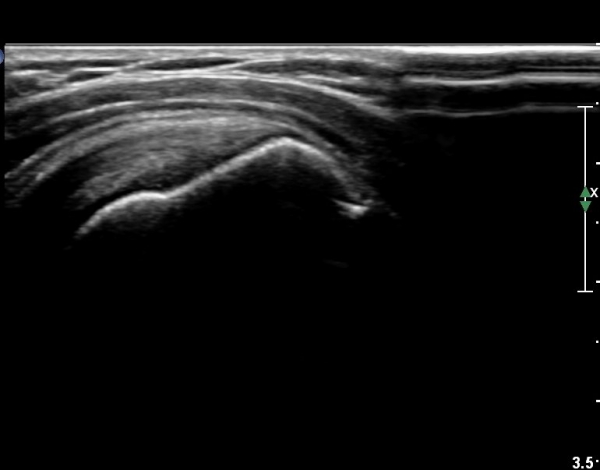

ÃÊÀ½ÆÄ ¼Ò°ß :  ±Ø»ó°Ç Á¾´Ü¸é°Ë»ç¿Í Ⱦ´Ü¸é°Ë»ç»ó ƯÀÌ ¼Ò°ß º¸ÀÌÁö ¾ÊÀ½(»çÁø 1, 2).